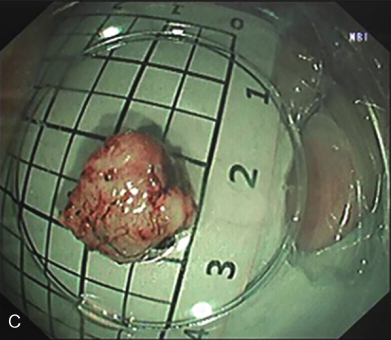

患者于2016年12月1日行“内镜下食管隆起性病变STER”,胃镜探查见食管距门齿33cm处扁平黏膜下隆起。手术步骤如下:①患者气管插管后全身麻醉,取左侧卧位。②镜身前端安装透明帽,冲洗并吸净食管腔内残渣及黏液。于瘤体周围黏膜下注射少量靛胭脂定位,并标记至肿瘤近口侧4~5cm处,作为切口。③予生理盐水、靛胭脂和肾上腺素混合液进行反复黏膜下注射,使切口处黏膜隆起(图2A)。应用Hook刀切开黏膜,内镜进入黏膜下逐步分离,在固有肌层和黏膜下层形成一纵行隧道。分离范围应超越瘤体2cm,充分暴露瘤体(图2B)。④使用Hook刀完整分离瘤体,注意保护肿瘤包膜完整,避免损伤食管外膜(图2C)。⑤取出瘤体后,反复冲洗,清理出血点,钛夹封闭黏膜切口。术后常规放置胃肠减压管。手术时间65min,术中出血15ml。

图2 内镜下食管隆起性病变STER

A.食管黏膜下肿物;B.建立隧道,暴露肿瘤;C.完整剥除肿瘤

-病理诊断:(食管)GIST(1cm×1cm×0.6cm),核分裂象0~1个/50HPF。改良NIH危险度分级:极低危。